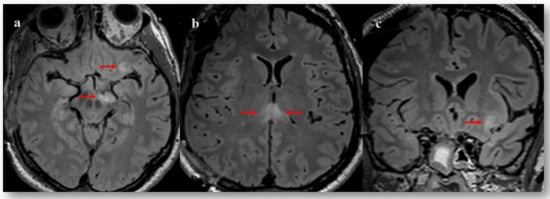

A neuroradiological evaluation confirmed these suspicions. MRI of the brain revealed a discrete extra-cranial cerebral herniation, perivenular haemorrhages of the left frontal cortical-subcortical junction and the corpus callosum suggesting traumatic haemorrhagic axonal lesions. There was also a restriction in the diffusion images of the splenium of the corpus callosum and the right cerebral peduncle, suggesting non-haemorrhagic traumatic axonal lesions. Finally, small oedemato-haemorrhagic contusion in the left orbito-frontal, left fusiform gyrus and right cerebellum were reported (Figure 2).

Figure 2.

Figure 2. Fluid attenuated inversion recovery (FLAIR) magnetic resonance imaging taken 13 days post-severe TBI. Axial and coronal sections showing areas of hyperintense signal (indicated with arrows) in the left cerebral peduncle (a), orbito-frontal cortex (a,c) and splenium of corpus callosum (b).